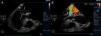

Transthoracic echocardiography (TTE) showed multiple aortic valve vegetations (some prolapsing into the left ventricular outflow tract), mild aortic regurgitation and a large saccular bulge originating from the anterior mitral valve leaflet and protruding into the left atrium with severe mitral regurgitation (Figure 1); left ventricular systolic function was normal. With transesophageal echocardiography (TEE) it became clear that the saccular bulging on the mitral valve was an anterior mitral valve leaflet aneurysm with two rupture sites (Figure 2). Color flow Doppler showed two regurgitant jets: one through the coaptation margin of the mitral valve leaflets and the other across the perforated aneurysm (Figure 3). There was no evidence of either aortic ring abscess formation or extension along the mitral-aortic intervalvular fibrosa.

Transesophageal echocardiogram (3-chamber view). (A) Ruptured aneurysm of the anterior mitral valve leaflet. The long arrow points to the entry site and the small arrow points to the exit site of the aneurysm; (B) color Doppler image showing two mitral regurgitation jets: a small jet through the leaflet coaptation point (small arrow) and a much more significant one through the aneurysm (long arrow).